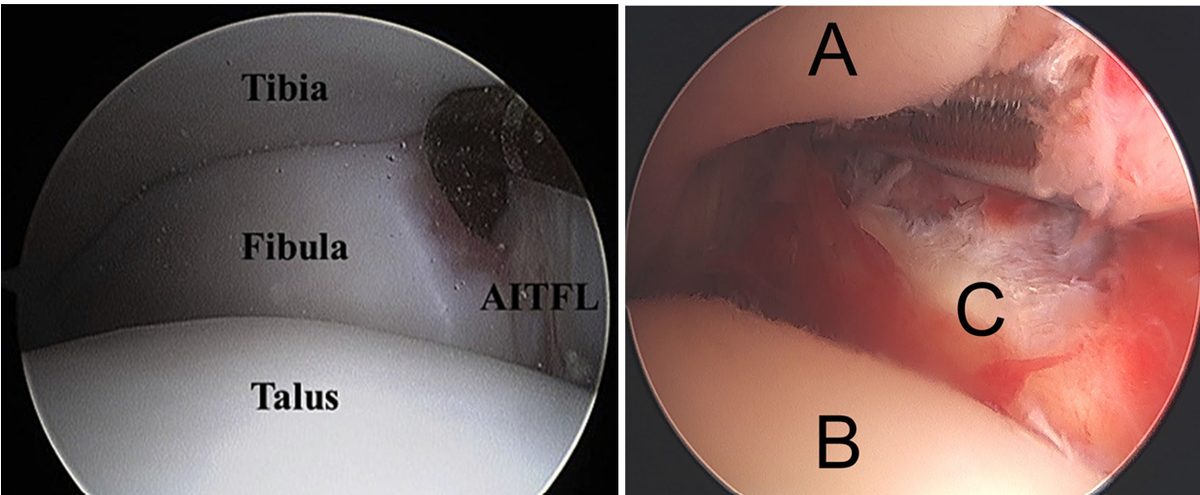

Артроскопия

Рис. 17. Артроскопический вид нормального и повреждённого синдесмоза

Артроскопическая оценка синдесмоза стала ценным методом диагностики стабильности связочного аппарата голеностопного сустава. Артроскопия обеспечивает прямую визуализацию межберцового сочленения и позволяет оценить стабильность в нескольких плоскостях — фронтальной, горизонтальной и сагиттальной — при моделировании нагрузок. Точность артроскопической диагностики повреждений синдесмоза составляет 100%.

Острые повреждения

Рис. 19. Возможные варианты подвывиха в межберцовом синдесмозе

При острых повреждениях можно визуализировать разорванные части передней порции синдесмоза и нестабильность малоберцовой кости, что позволяет определить характер повреждения и выбрать адекватную тактику лечения.

Артроскопически выделяют: частичный разрыв ПНБМс, полный разрыв ПНБМс без дислокации, полный разрыв ПНБМс с дислокацией, полный разрыв ПНБМс с отрывом ЗНБМС. Помимо латерального повреждения, артроскопия позволяет оценить состояние дельтовидной связки и стабильность всей вилки.